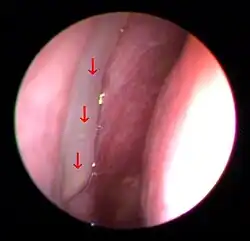

In the absence of any specific diagnostic tests, it may be difficult to diagnose PND from history of symptoms alone, as the etiology is broad and the symptoms may be very general. As such, suggestive procedures that highlight rhinitis and mucopurulent secretions, such as nasoendoscopy, may instead be utilized because of the vague nature of information available to directly attribute specific symptoms to the syndrome.[12][2] In patients with accessory ostium recirculation, a condition often overlooked, careful nasal endoscopy may sometimes reveal a characteristic ring of mucus flow between adjacent openings.[10]